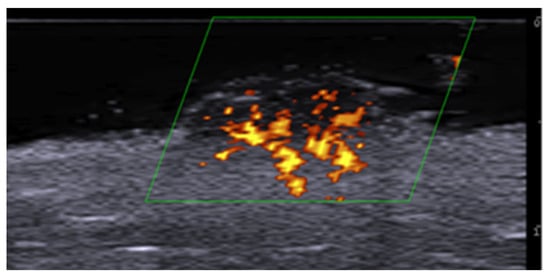

5. Specific Cutaneous Structure and Sites of Skin Disorders